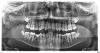

Oleg-Gru Опубликовано 23 июля, 2012 Поделиться Опубликовано 23 июля, 2012 (изменено) Доброго времени суток, уважаемые стоматологи! Уже не в первый раз обращаюсь к помощи форума. Как и раньше, очень надеюсь на квалифицированный совет. Суть проблемы: Пациент: Мальчик, возраст 14,5 лет.Диагноз: Дистальный прикус, (Класс 2-1), сагитальная щель, Первичная адентия 35,45. Ретенция 75, 85. Тортопозиция 13,12,22,23. Доктор №1 предлагает: удаление молочных моляров на нижней челюсти и первых премоляров на верхней челюсти. Ортодонтическое лечение с целью распределения зубов по дуге: мезиализация дистальной группы зубов на обеих челюстях до полного устранения трем. Поворот 13, 12, 22, 23 и установление в правильное положение. Доктор №2 опасается, что удаление верхних первых премоляров скажутся отрицательно на лицевом профиле. Поэтому, предлагает удалить только нижние молочные моляры. После чего провести мезиализацию нижних моляров с целью закрытия трем. Восстановить фиссурно-бугорковый контакт путем сошлифовывания бугров зубов. (Т.е. совместить нижние 6ки и верхние 5ки). Соответственно стоит нетривиальная задача: какой план лечения выбрать? Вариант с последующей установкай имплантантов не принимается в силу возраста пациента. Буду признателен за любое квалифицированное мнение. С уважением,Олег. Изменено 23 июля, 2012 пользователем Oleg-Gru Ссылка на комментарий

Skip Опубликовано 24 июля, 2012 Поделиться Опубликовано 24 июля, 2012 Неужели вариант №2 (с мезиализацией нижних моляров) совсем не подходит? Да ерунда всё это. C этой "мезиализацией", а в реальности там получится банальный наклон зубов в сторону промежутка, в результате чего произойдёт углубление передне-задней окклюзионной кривой (Spee), что будет убийственным для суставов, в которых сейчас и так происходит компрессионный ремоделинг. Каждый зуб должен стоять на своём законном месте. Угробив этой мезиализацией (плюс стачивание бугров) ВНЧС, к 30 годам он будет не только без премоляров, но и части жевательной группы зубов, вот Вы его от пожизненных мучений избавите. Я нисколько не преувеличиваю, т.к. вижу это у себя в офисе ежедневно вот уже более 20 лет. Решайте сами... Залогом долговечности ортопедических конструкций, в том числе и имплантатов, служит ряд факторов, критическими из которых являются:1. Нормально функционирующее ВНЧС.2. Идеализация пространственной ориентации окклюзионной плоскости.3. Траектория нижнечелюстного пути без замедления в скорости и отклонений. Если с этой троицей есть проблемы, то проблемы будут не только с коронками и имплантатами, но и с живыми зубами. Обратите внимание, как на ТРГ раздваивается нижний контур основания нижней челюсти. Посмотрите на ОПТГ, где нижняя челюсть стоит косо и отклоняется вправо. Вас должно беспокоить это обстоятельство в большей степени, чем два отсутствующих премоляра, т.к. это не проблема. Ссылка на комментарий

Force Опубликовано 25 июля, 2012 Поделиться Опубликовано 25 июля, 2012 (изменено) Добавить могу только рекомендацию по удалению зачатков нижних восьмерок, поскольку дальнейшее их формирование приведет к скученности на нижней челюсти и деформации окклюзионной плоскости. Резорбции корней нижних молочных моляров нет, поэтому нет предпосылок, что эти зубы скоро покинут рот. Пусть себе живут. Единственное, они больше размером чем постоянные пятерки, поэтому некоторые западные ортодонты рекомендуют подшлифовать их с контактных поверхностей, чтобы шестерки встали на свои места.Когда они разрушатся и будут удалены - имплантация. Мезиализация нижних моляров - неудачный эксперимент. Стратегически Алексей Олегович прав, это кейс для функционального аппарата. Информация дана с избытком Твинблок, твинфорс, форсус, гербст - чем доктор умеет. Никаких удалений премоляров! Изменено 25 июля, 2012 пользователем Force Ссылка на комментарий